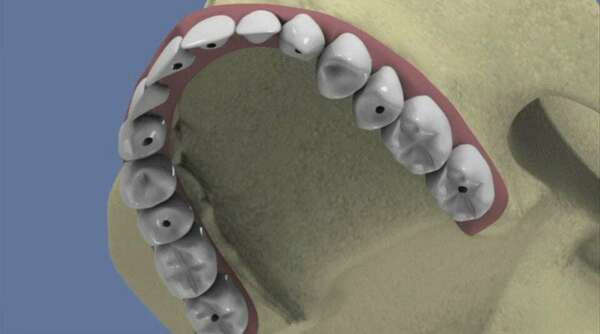

Retrouvez le sourire ! Grâce aux implants dentaires, solution pour stabiliser un bridge, remplacer un appareil dentaire, ou une dent. Lisez et contactez le cabinet dentaire des docteurs Brandt à Sarreguemines !